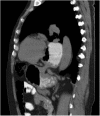

Presentation of case: We report the case of a 61 year old, healthy male, referred to surgical consultation complaining of epigastric discomfort and postprandial fullness. The diagnostic workup showed a mesentero-axial volvulus of the stomach. He was operated electively: reduction of volvulus, Nissen fundoplication and gastropexy was performed, with resolution of symptoms.